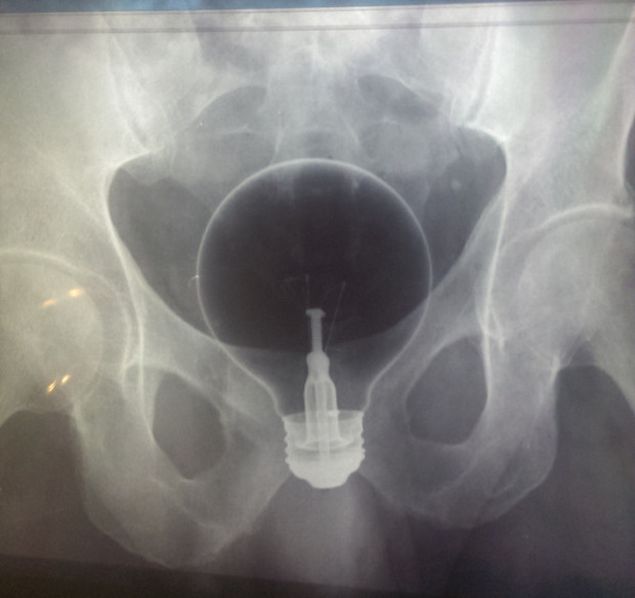

Un barbat s-a prezentat cu un bec in anus, iar potrivit spuselor medicilor, becul s-a spart in momentul in care a fost extras.